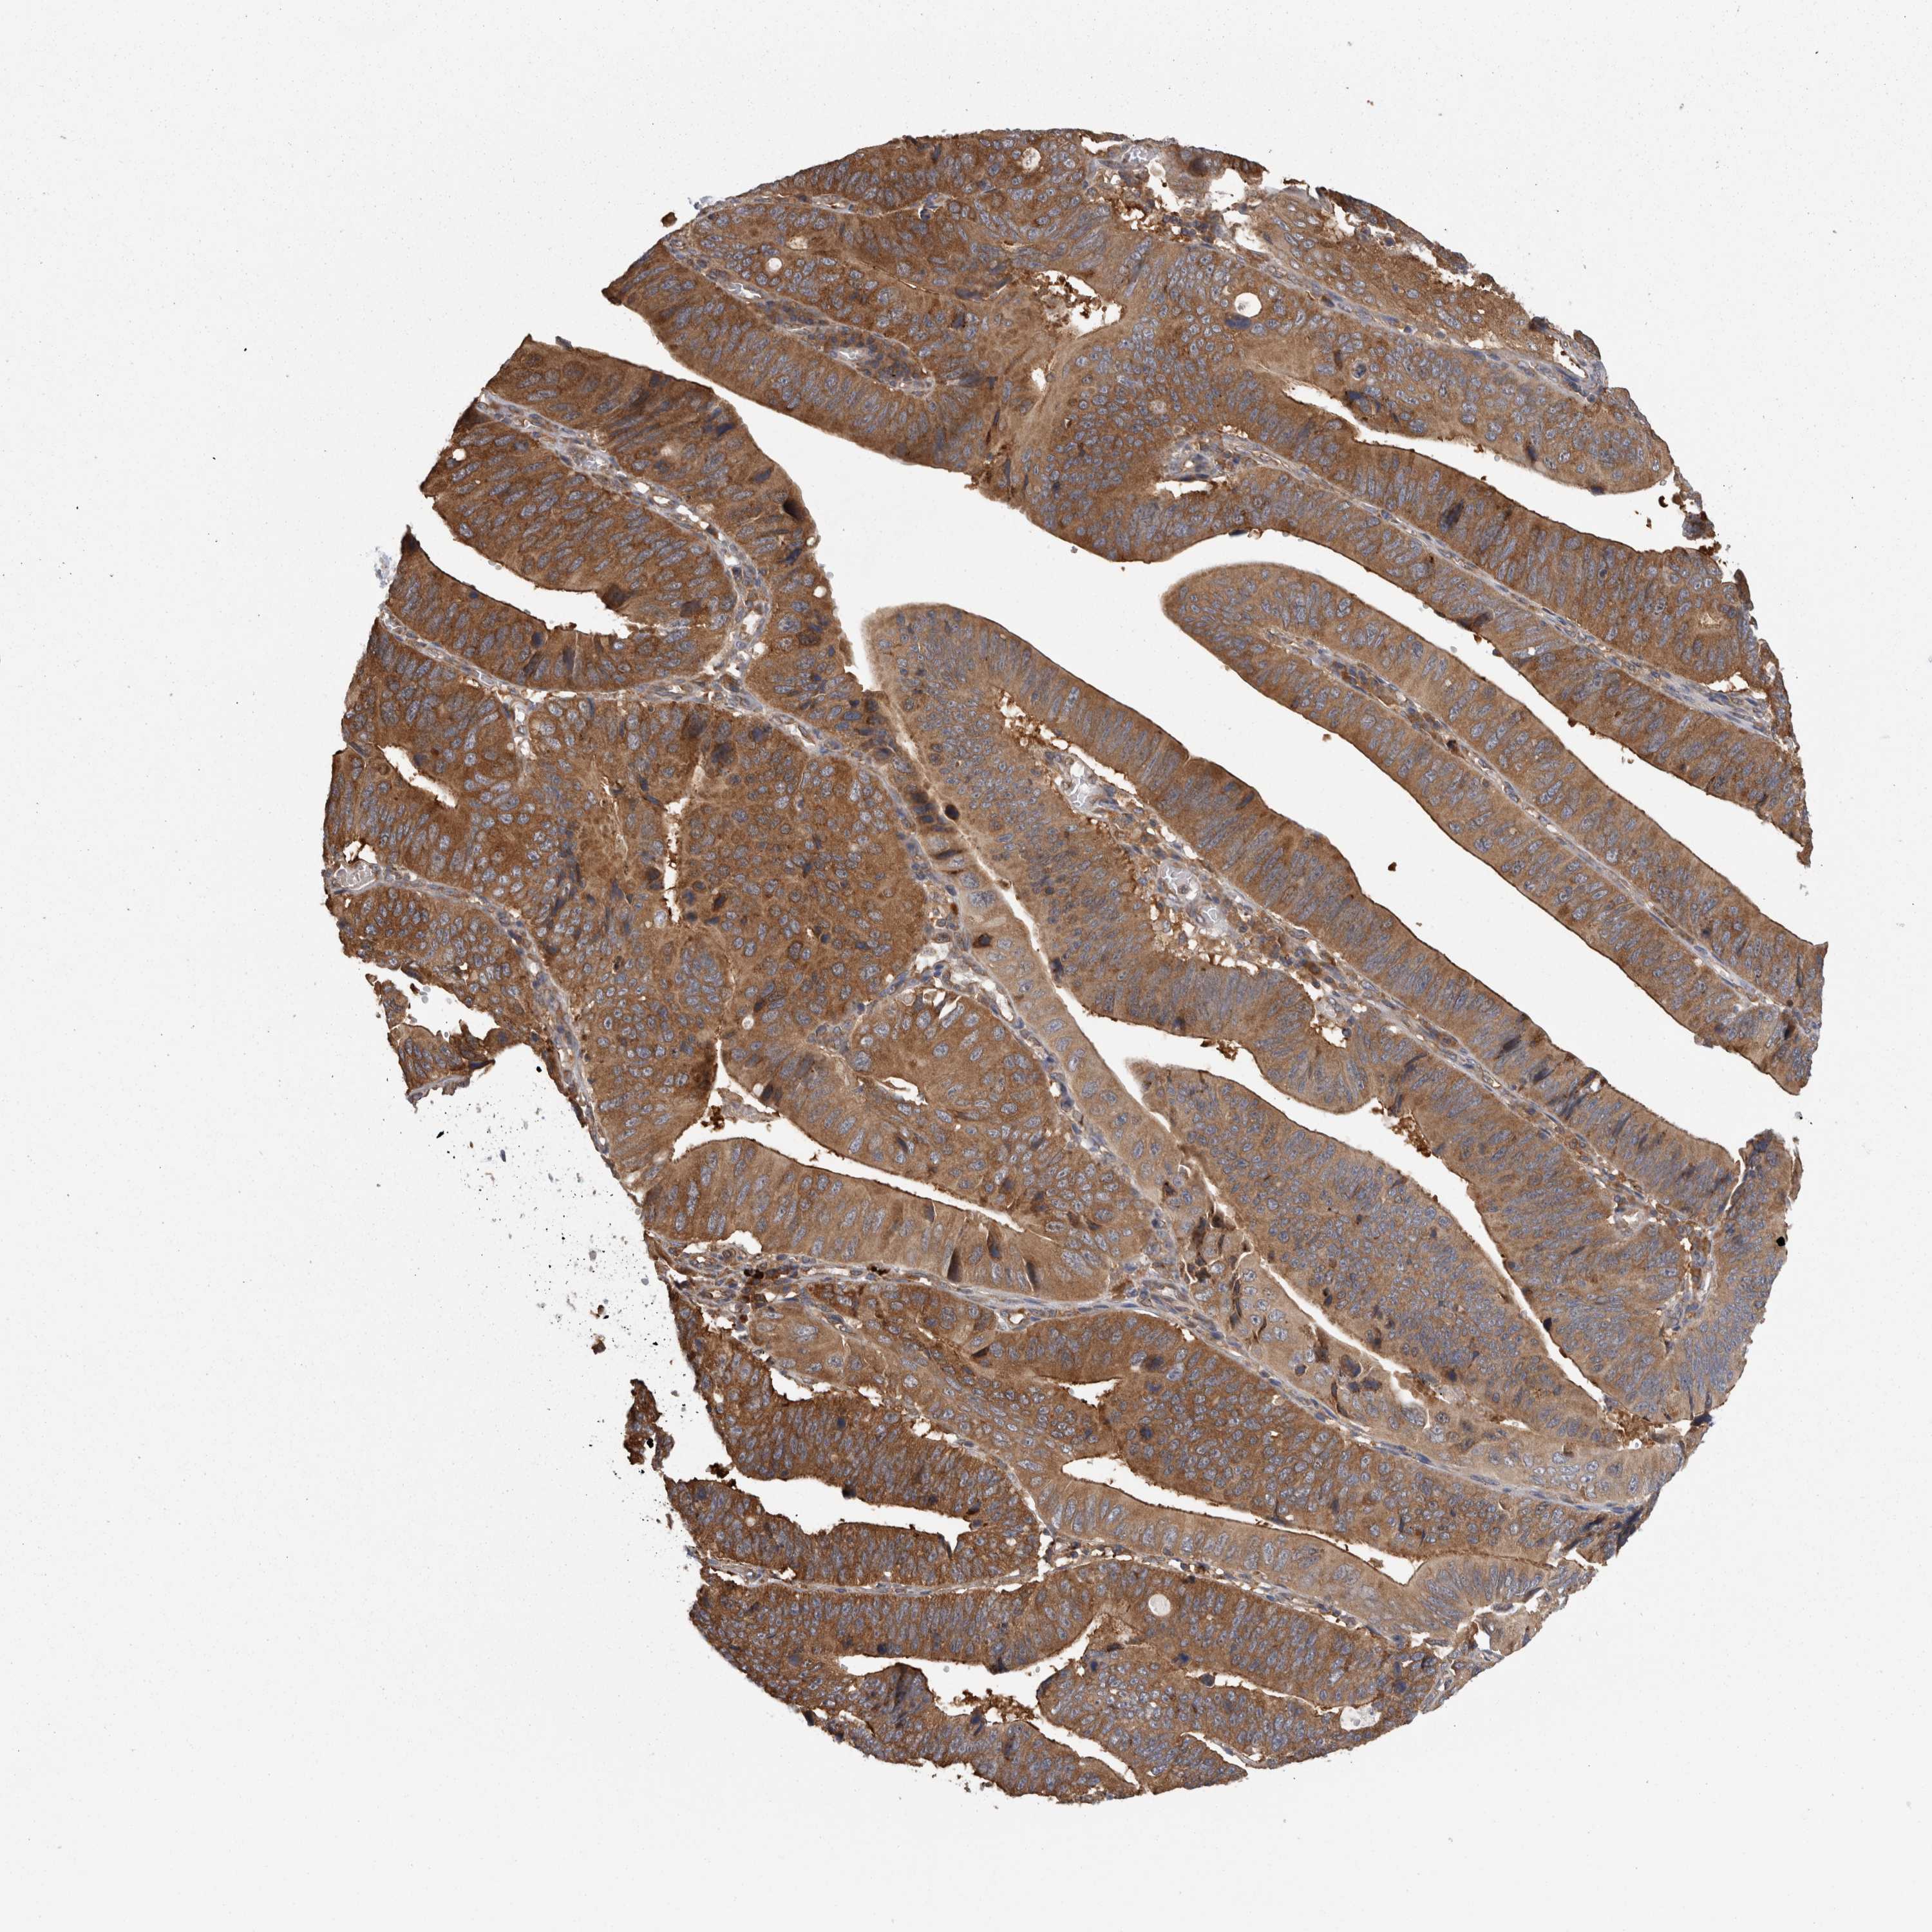

STOMACH CANCER - Protein expressioni

A mouse-over function shows sample information and annotation data. Click on an image to view it in a full screen mode. Samples can be filtered based on level of antibody staining by selecting one or several of the following categories: high, medium, low and not detected. The assay and annotation is described here.

Note that samples used for immunohistochemistry by the Human Protein Atlas do not correspond to samples in the TCGA dataset.

Antibody stainingi

Antibody staining in the annotated cell types in the current human tissue is reported as not detected, low, medium, or high, based on conventional immunohistochemistry profiling in selected tissues. This score is based on the combination of the staining intensity and fraction of stained cells.

Each image is clickable and will lead to virtual microscopy that enables deeper exploration of all samples and also displays staining intensity scores, fraction scores and subcellular localization as well as patient and tissue information for each sample.

Antibody HPA021557

Antibody HPA024646

Staining

High

Medium

Low

Not detected

Intensity

Strong

Moderate

Weak

Negative

Quantity

>75%

75%-25%

<25%

None

Location

Nuclear

Cytoplasmic/membranous

Cytoplasmic/membranous,nuclear

Adenocarcinoma, NOS